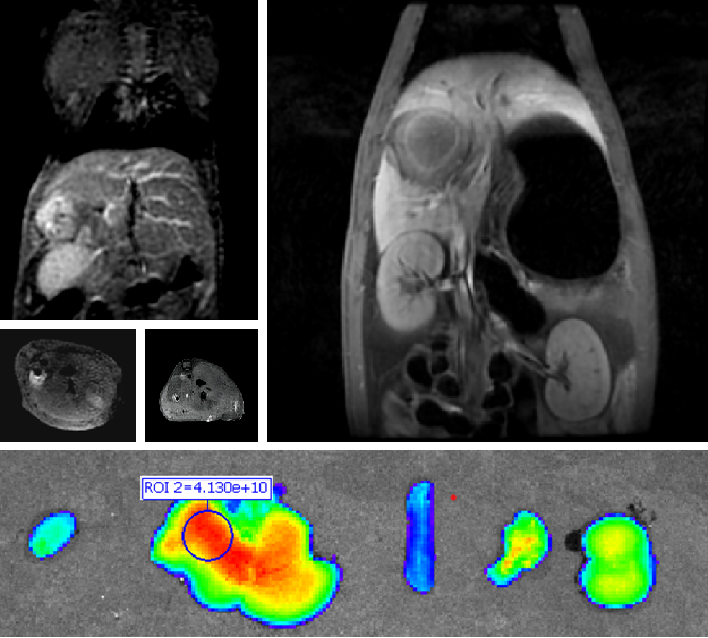

PL002是浙江3044am永利官网药业有限公司研发的荧光/磁共振双模态造影剂,开发荧光/磁共振双模态造影剂成为提高原发性肝癌手术效率的有效方案。双模态造影剂的荧光成像能力可用于肝癌术中荧光导航,而磁共振增强能力可用于在术前判断肝脏代谢能力,推测肿瘤及肝脏对造影剂的摄取情况,提高肿瘤诊断精度,降低术前规划难度。

PL002相较于吲哚菁绿具有明显优势。目前吲哚菁绿在临床使用中存在给药到手术时间不确定的问题,可能造成病灶与正常组织对比度不足,影响术中的病灶的判断,PL002采用独特的钆络合物与荧光分子共价键结合的分子结构设计,这种设计能够让医生在术前通过磁共振成像确定造影剂在病灶中的聚集情况,进而针对患者个体情况来对手术时间进行规划。同时,由于PL002体内更为稳定,在荷瘤小鼠模型中同等条件下荧光成像效果维持时间长于现有荧光造影剂,也保证了其在临床应用中具有更宽的手术窗口。

使用双模态造影剂可以为手术医生提供更加丰富的诊断信息,降低术中的决策压力,避免过度切成,增加发现微小病灶的可能性,最终实现患者的全面获益。此外,相较于传统荧光造影剂,PL002的安全性更高、体内更为稳定,成像效果更佳,为其临床使用提供了有效的支持。